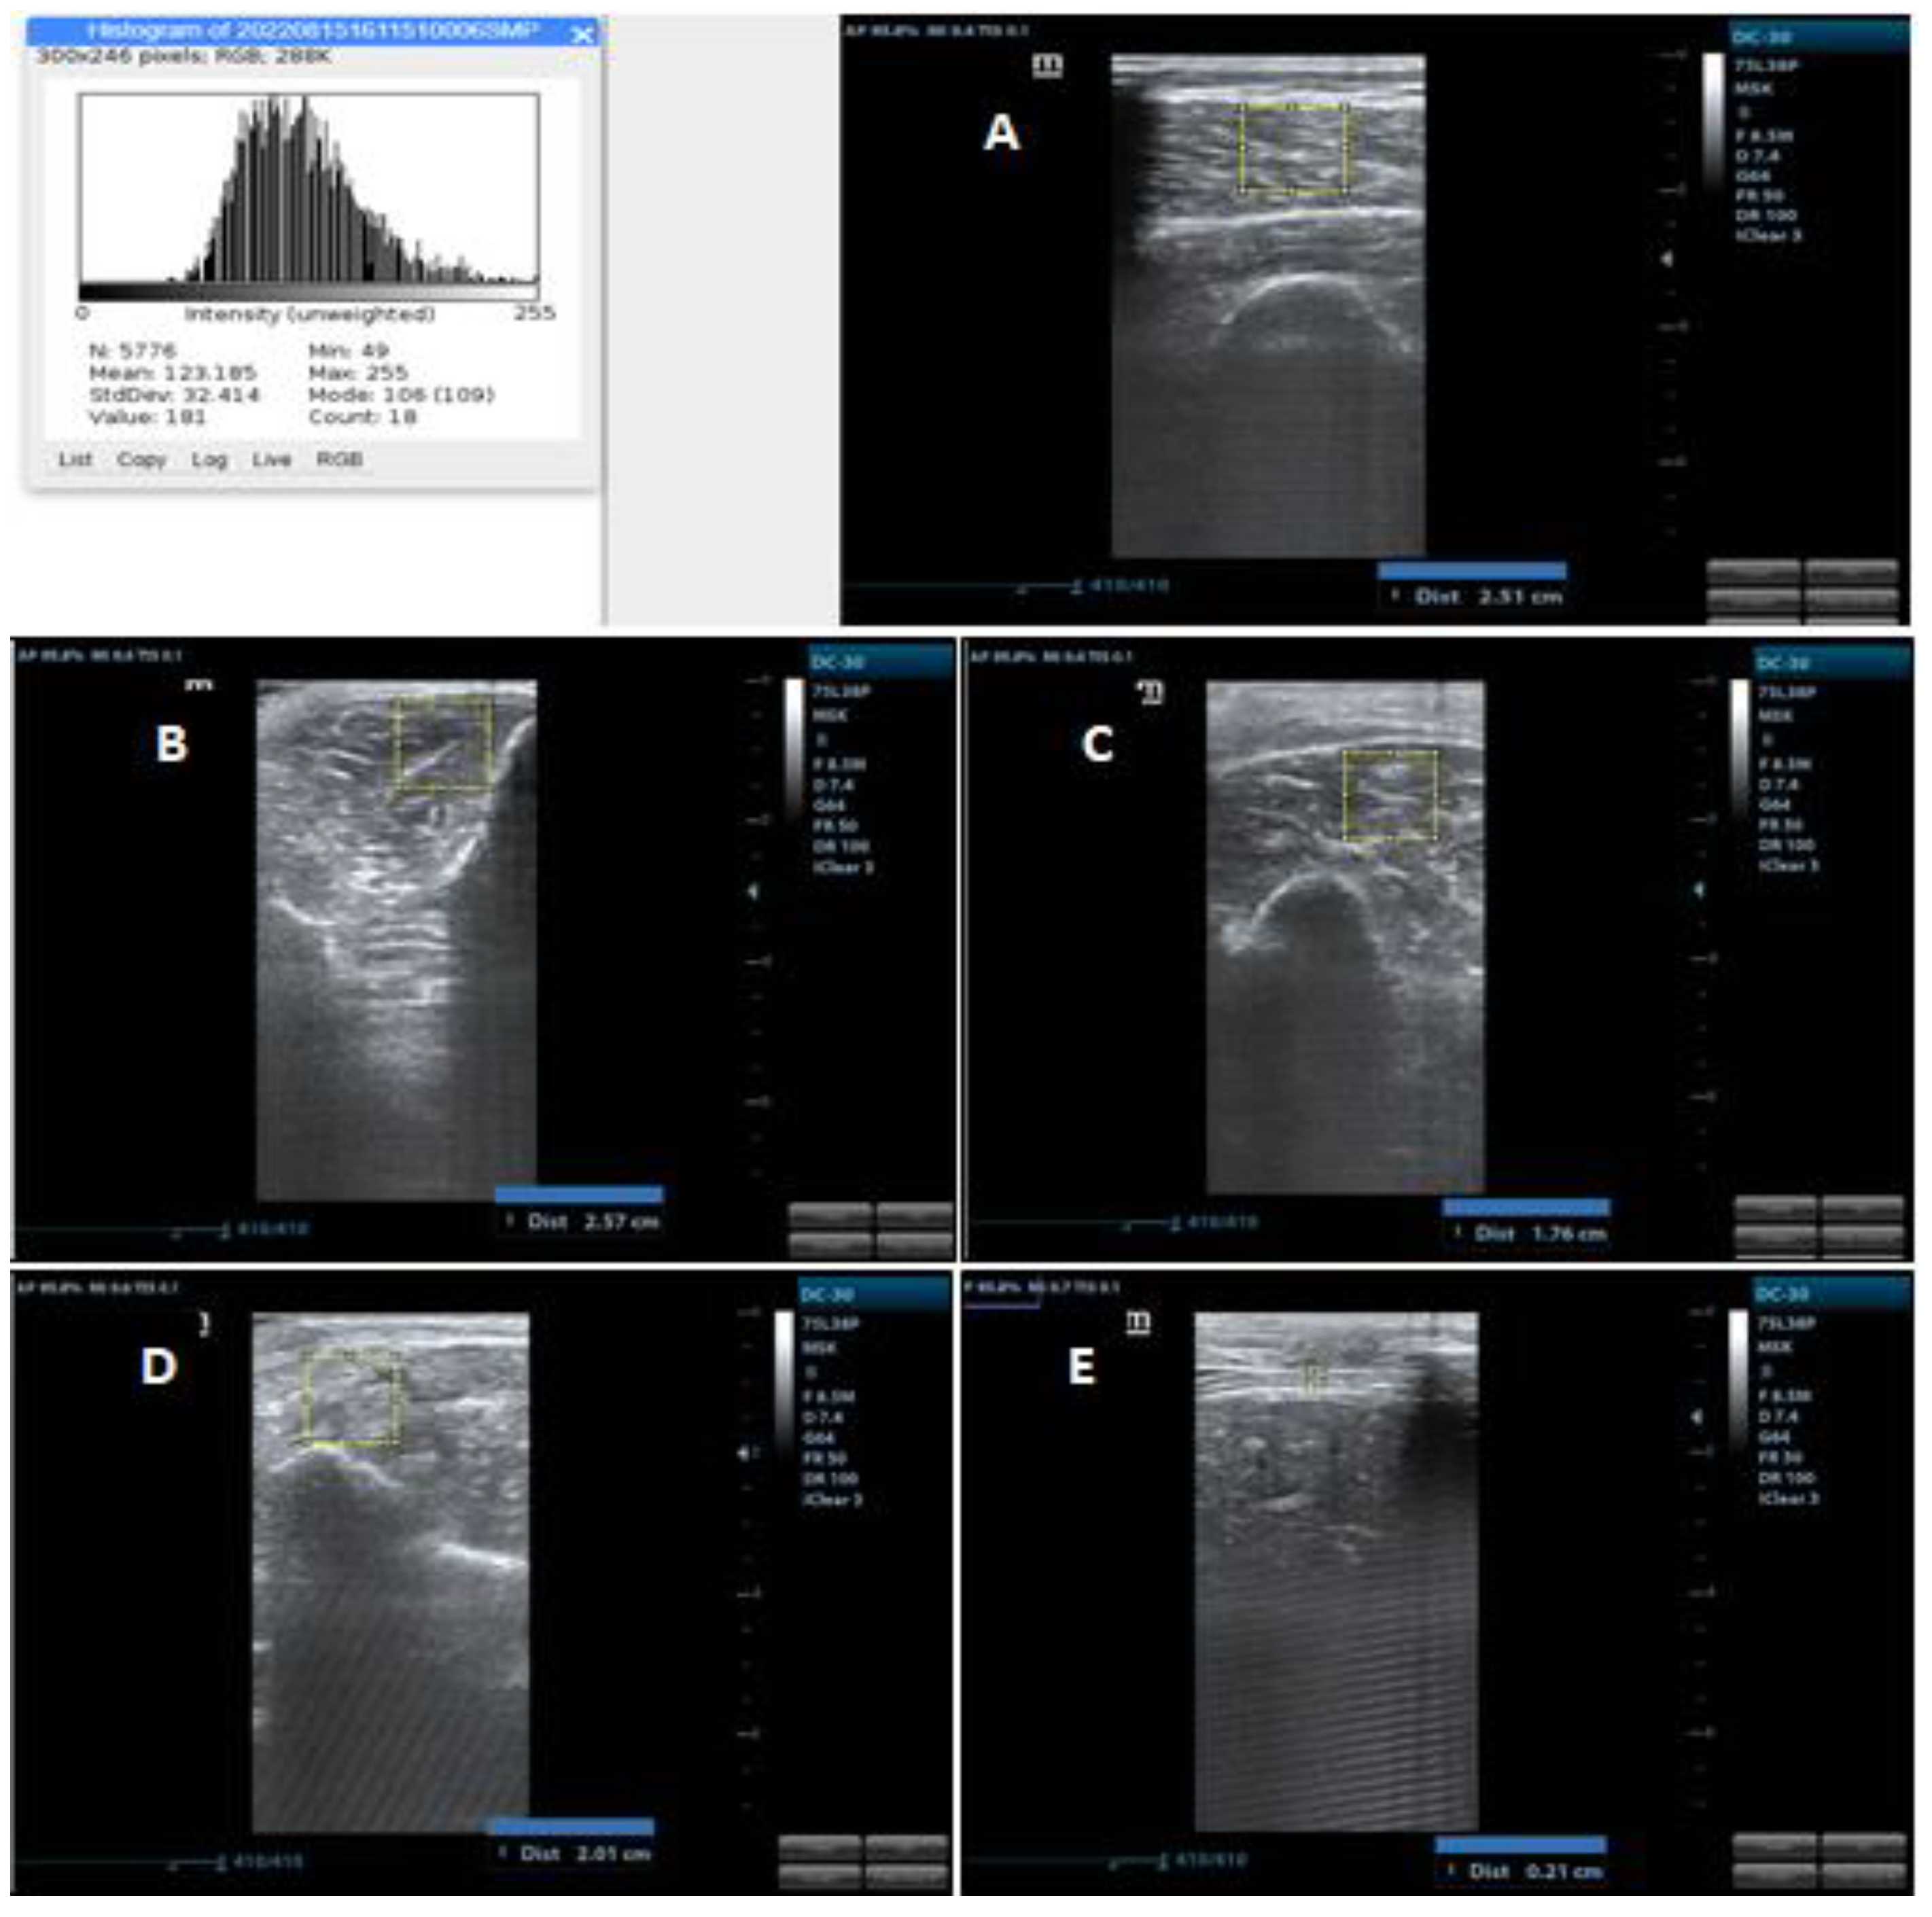

The thickness of the biceps brachii muscle was assessed between the upper part of the humerus and the superficial fascia of the biceps (including the brachialis muscle); on the forearm flexor group, it was evaluated between the interosseous membrane located close to the radius and the superficial fascia of the flexors; on the quadriceps femoris it was evaluated between the upper part of the femur and the superficial fascia of the rectus femoris (includes the rectus femoris and vastus intermedius); finally, on the tibialis anterior it was evaluated between the interosseous membrane located close to the tibia and the superficial fascia of the tibialis anterior [25]. Measurements were performed in centimeters and can be seen in Figure 2.

Figure 2.

US image demonstrating various measurements of muscle thickness and echogenicity. Source: authors. (A) Quadriceps femoris US image with thickness measurement and histogram; (B) Tibialis anterior US image with thickness measurement; (C) Biceps Brachii US image with thickness measurement; (D) Forearm flexor groups US image with thickness measurement; (E) Diaphragm US image with thickness measurement.

Muscle echogenicity was quantified using the grayscale analysis histogram through the square trace method using the ImageJ software in a region of interest with an area of 2 cm × 2 cm for the peripheral muscles and 1 cm × 1 cm for the diaphragm. In muscles where the square was not allowed in the indicated measurements, the largest possible square area was examined within the anatomical limits established for the evaluated muscles. This area was used to reduce the risk of using structures other than the muscle of interest, such as fascia and bone. In grayscale analysis, black is assigned 0, and white is assigned 255, with shades of gray in between and each pixel is assigned a value. This allows the mean and standard deviation of grayscale values to be calculated, which was repeated 3 times for each muscle [27]. Images used for echogenicity analyses were selected from those used for the assessment of muscle thickness, using only the images of one examiner, which was randomly chosen. Measurements can be seen in Figure 1. As the training did not include the echogenicity assessment, only the examiner who had experience with the assessment and use of ImageJ carried out the analysis, so only the intra-examiner reliability was performed.